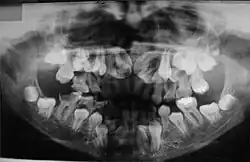

O diagnóstico do portador de DCC é realizado através de exames clínicos e radiográficos. A aparência clínica dos acometidos é bastante característica, principalmente após a puberdade devido a alguns traços dessa doença, como baixa estatura, falha na erupção dos dentes permanentes, dentes supranumerários e retardo na esfoliação dos dentes decíduos. Outros aspectos dessa patologia são: a aplasia ou hipoplasia clavicular (clavículas rudimentares ou completamente ausentes), que está presente em 10% dos casos, que permite o movimento do braço até ao plano sagital mediano. A abóboda craniana aumentada, uma menor espessura do músculo masseter, hipodesenvolvimento do terço médio da face, geralmente também é apresentado uma hipoplasia da maxila, retardo no desenvolvimento esquelético, o pescoço largo e atraso no fechamento das suturas cranianas. Em alguns casos é possível observar que os palatos estreitos e profundos também são frequentes. É importante realizar o diagnóstico diferencial devido aos pacientes exibirem nanismo, ossos densos, frágeis e agenesias parciais das falanges dos dedos dos pés e mãos.[9][10]

No estudo realizado por McNamara et al. (1999) sobre as características da síndrome, encontradas nas radiografias panorâmicas, citam-se a presença de múltiplos dentes não irrompidos; dentes com alterações de forma; ramos ascendentes da mandíbula delgados com os bordos posterior e anterior paralelos e, em alguns casos, estreitando-se em direção ao processo coronóide e côndilo; processo coronóide frequentemente ascendente e para posterior; arco zigomático estreito com severa inclinação descendente e algumas vezes descontínuo com a sutura zigomático-temporal; seios maxilares pequenos ou ausentes; bordo infraorbital mais baixo que o normal em relação aos dentes; inclinação descendente do assoalho da fossa nasal em relação à espinha nasal anterior, acentuando a forma em V; trabeculado ósseo da mandíbula com aspecto grosseiro; aumento da densidade da crista óssea alveolar, comprometendo a irrupção dentária; aumento da densidade do ramo ascendente entre o bordo anterior da mandíbula e o canal dentário inferior. A maior parte dos pacientes com disostose cleidocraniana desempenha suas funções normais, não apresentando comprometimento significativo. Existem relatos de que o tratamento cirúrgico com a exposição dos dentes inclusos, combinado com o tratamento ortodôntico, tem sido bem-sucedido em alguns casos (McDONALD, 2001). Porém, a extração dos dentes decíduos não promove a erupção dos dentes permanentes inclusos.[11]

Sabe-se que a retenção prolongada dos dentes decíduos, agenesias e dentes supranumerários provocam má oclusão. Portanto, procedimentos ortodônticos devem ser utilizados com a finalidade de adequar a cavidade bucal para futura reabilitação protética. Os exames radiográficos, além de auxiliar na detecção das anormalidades maxilofaciais, permitem o acompanhamento dos pacientes, sendo, por isso, considerados uma ferramenta para o diagnóstico e conduta terapêutica.[11]

As anomalias orais causadas pela disostose cleidocrania são marcantes, e geralmente, são fatores determinantes para o diagnóstico da DCC, tornando o cirurgião-dentista parte crucial para a descoberta da doença.[12] Estas anormalidades apresentadas pelos pacientes que possuem disostose são numerosas e estão presentes principalmente na dentição decídua, mas também podem aparecer na permanente. São elas: Anodontia parcial (ausência do elemento dentário), dentes supranumerários, erupções tardias, dentição ectópica (fora do local adequado) e anomalias dentárias, palato alto, estreito e arqueado, assim como, subdesenvolvimento da maxila e seios paranasais, alteração de densidade óssea e aumento da espessura da fibromucosa (gengiva)[13],[8],[14],.[12]

A erupção dos dentes permanentes pode ser afetada, pela permanêcia prolongada dos dentes decíduos no rebordo alveolar, em razão da presença de espesso tecido fibromucoso e densidade óssea, isso dificulta o aparecimento desses dentes na cavidade bucal apesar de os processos de formação, maturação e erupção dentária serem normais[13],[14]. Além disso o aparecimento de dentes supranumerários, em razão do atraso na reabsorção da lâmina dentária, também pode afetar a dentição permanente.[14]

Os dentes supranumerários, é como são chamados os dentes que excedem o número natural, essa quantidade varia e podem ser desde 1 a 30, e até mesmo 63 dentes excedentes encontrados. Essa quantidade anormal de dentes pode causar apinhamento, em decorrência da falta de espaço, e consequentemente má oclusão, bem como comprometimento das articulações, da mastigação e estética.[13]

O osso mandibular possui maior probabilidade de possuir dentes supranumerários, porém, também estão presentes nas maxilas. Além disso, estes dentes podem aparecer erupcionados ou inclusos, sejam decíduos ou permanentes, e isso causa uma movimentação nos dentes permanentes para além do local de oclusão, a denominada dentição ectópica[13],[8].